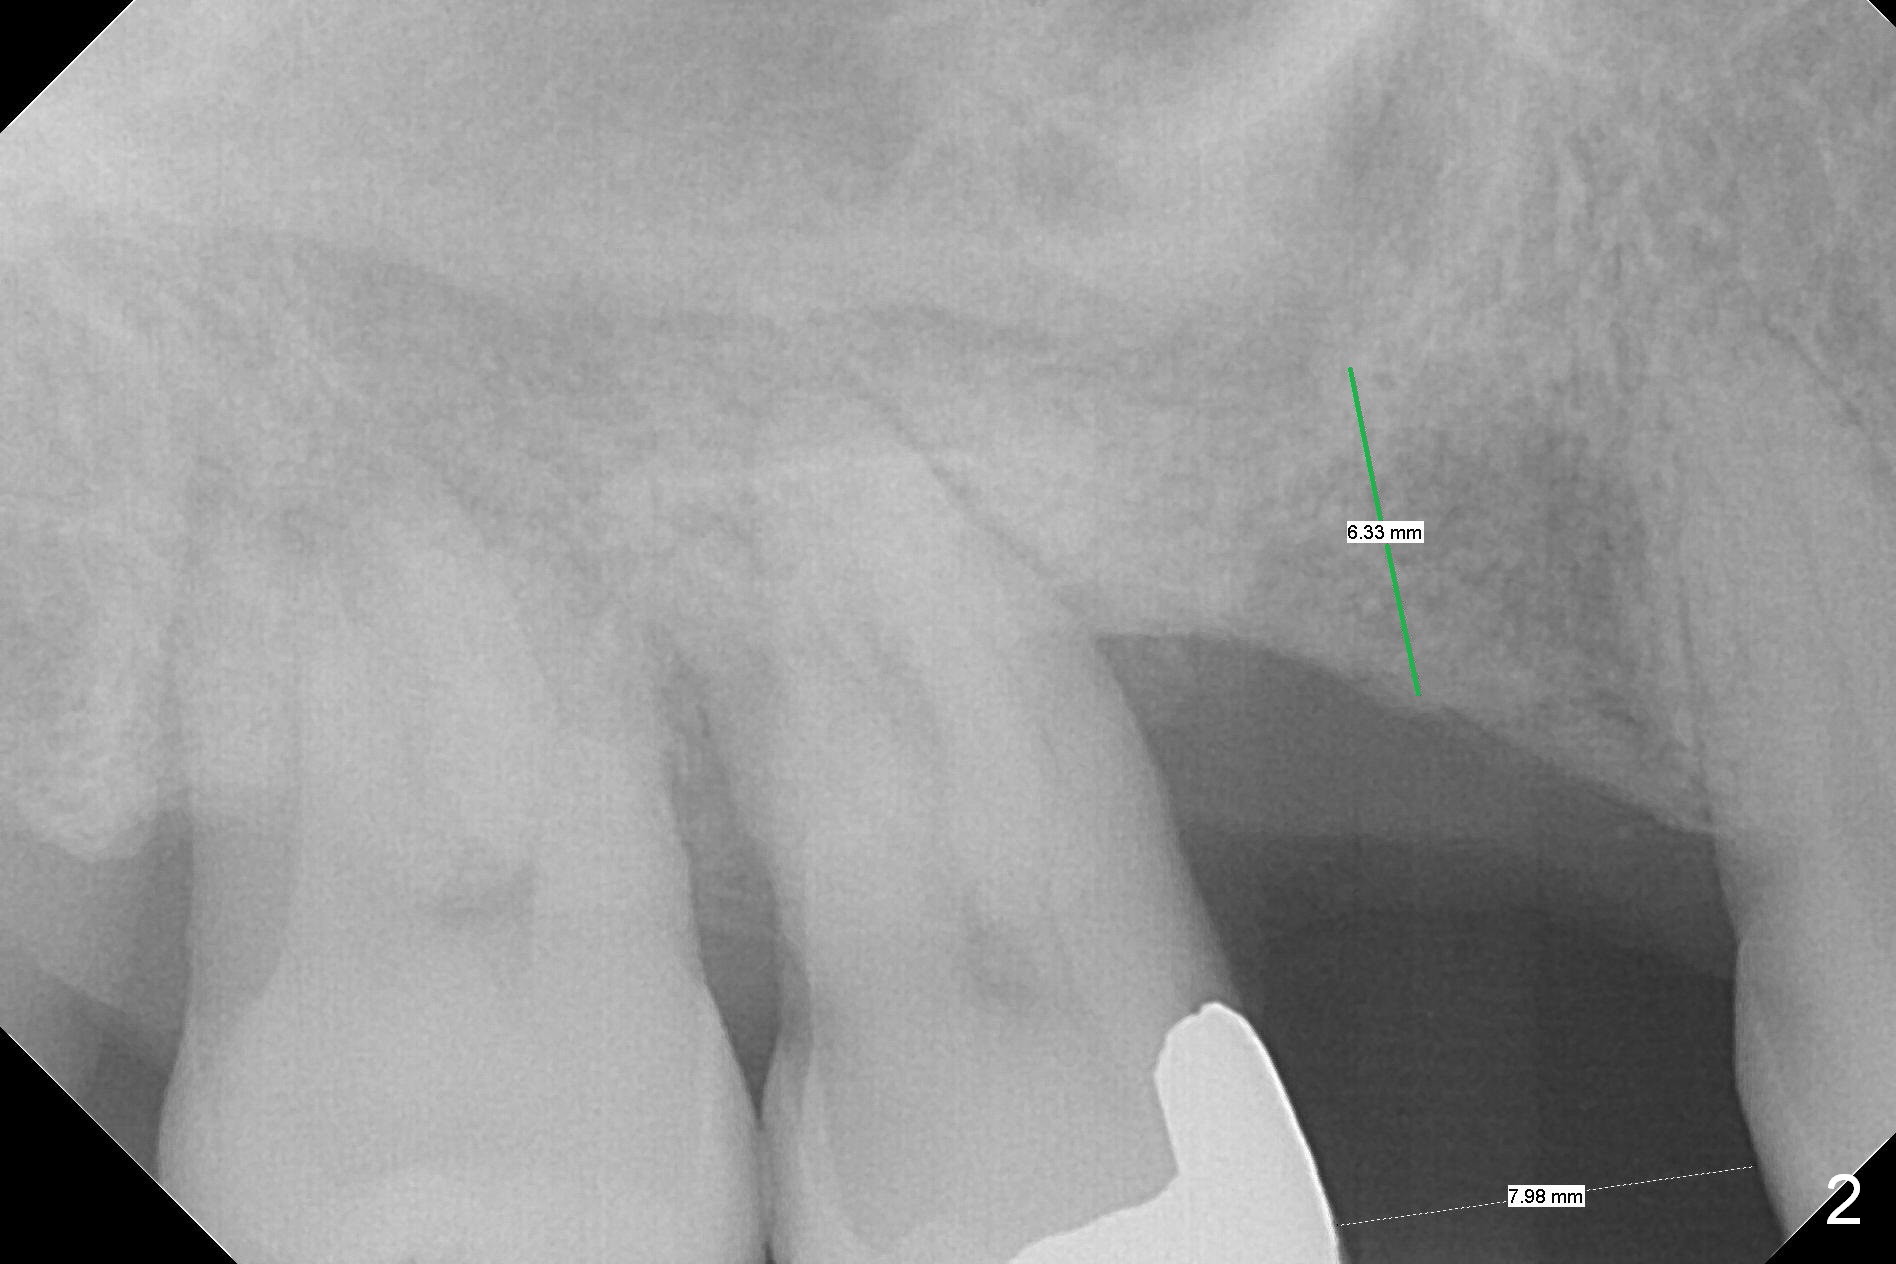

A 53-year-old man wants treatment so that the tooth #2 will not have the fate of the tooth #3. It appears that etiology includes periodontitis and occlusal trauma (Fig.1, 2). The tooth #2 has shifted mesially (Fig.1 ^). The initial drill of DIO Sinus Lift Master Kit will be used for 6 mm (Fig.2), followed by round burs for 7 mm or more. Place PRF and allograft (Metronidazole) before implant placement.